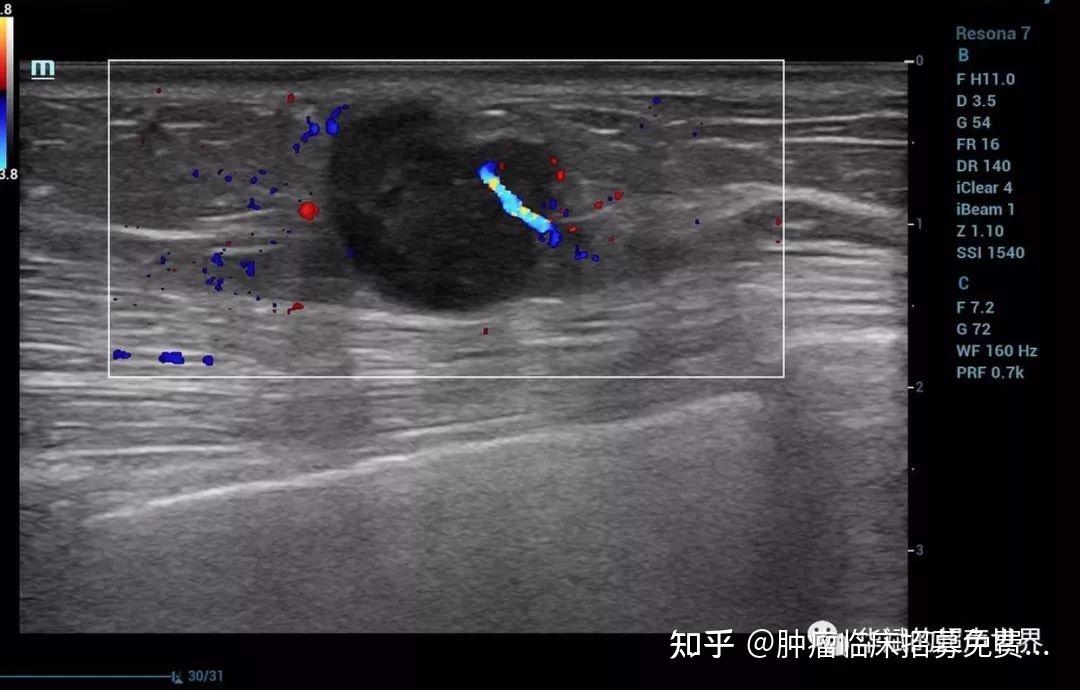

三阴乳腺癌的声像图特点及经典病例分享

图片尺寸1080x690